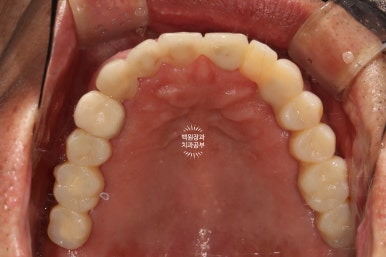

구강내 교합면 사진입니다.

모든 치아가 지르코니아 크라운으로 제작되어, 진짜 자연치같은 형태를 재현해내고 있습니다.

지르코니아 크라운운 캐드캠으로 제작되기 때문에 상당히 자연치와 유사한 형태와 색감을 냅니다.

임상적으로 아주 만족스러운 결과네요.